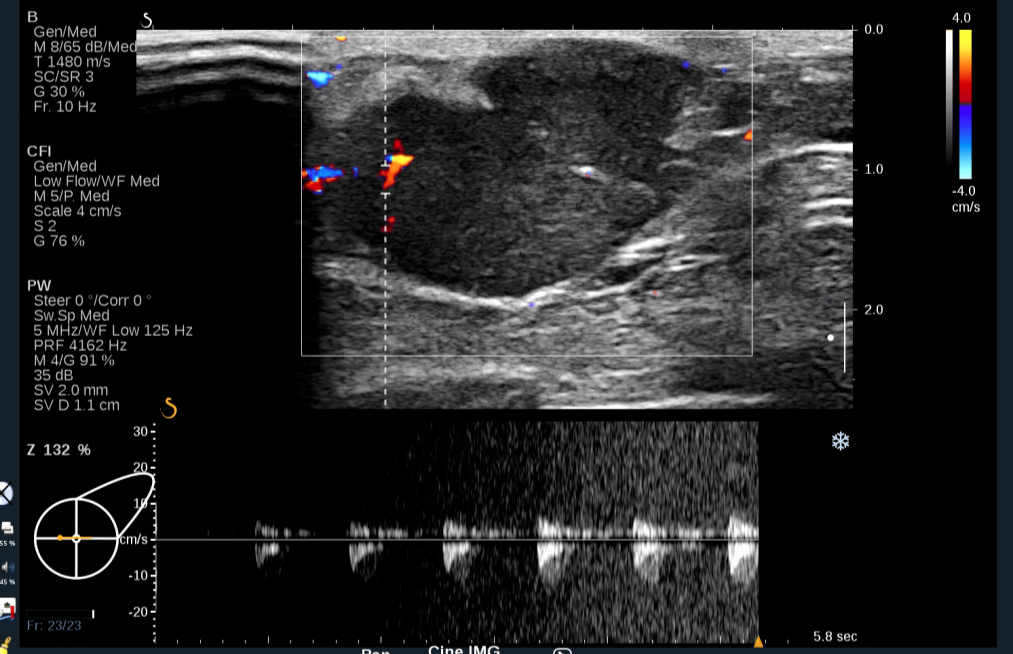

彩色多普勒及能量图:低回声团周边可见条形血流信号,并可测得动脉频谱,其内可见短棒状血流信号。

图4 频谱多普勒血流图示左乳肿块周边血管呈高阻力的动脉供血

图片来源:作者提供